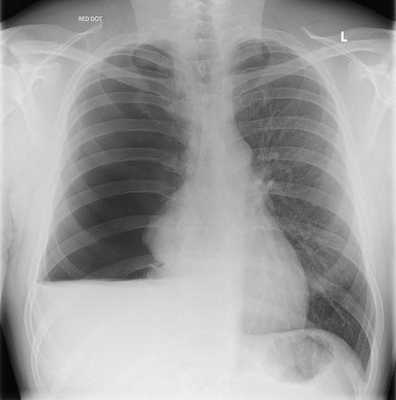

Скопление жидкости в плевральной полости. Рентгенография.

- Рентгенография. На снимках хорошо видна жидкость в плевральной полости и ее верхний уровень. Если гидроторакс связан с онкологическим заболеванием, рентгенография помогает обнаружить пораженные раком лимфатические узлы.

Безусловно, важным моментом является выявление причинно-следственных факторов— дисфагии, эпизодов нарушения сознания и пр., на фоне которых появилась клиническая симптоматика. Необходимо также учитывать результаты рентгенографии органов грудной клетки, проводимой в обязательном порядке в прямой и боковой проекциях. Чаще всего инфильтративные изменения с очагом некроза паренхимы легкого наблюдаются в тех сегментах легких, которые связаны с так называемым «гравитационным механизмом» (локализация абсцесса в заднем сегменте верхней доли, если аспирация произошла в положении лежа, или верхнем сегменте нижней доли, если аспирация произошла в положении сидя). Определенную роль играет интерпретация результатов общего исследования полученной мокроты— цвет, запах, присутствие крови и пр.

Вслед за некротизирующей пневмонией формируется собственно абсцесс легкого, что сопровождается такими симптомами, как лихорадка, анорексия, похудание, возможная анемизация, плевральные боли, экспекторация «гнилостной» мокроты. Завершает диагностику формирующегося или сформировавшегося абсцесса легкого визуализация толстостенных полостных образований диаметром более 1,0 см с характерным уровнем жидкости и газа. У ряда больных, особенно в случае прилежания полости абсцесса к плевре, нередко происходит спонтанное дренирование полости абсцесса с закономерным формированием эмпиемы плевры.

Из анамнеза заболевания известно, что заболел остро в начале августа 2007 г., когда после переохлаждения температура тела повысилась до фебрильных цифр, появились озноб, боль в левой половине грудной клетки, усиливающаяся при движениях, перемене положения тела, выраженная слабость, непродуктивный кашель. Обратился в поликлинику по месту жительства, где с 8.08.07 по 13.08.07 г. проходил лечение у невролога по поводу межреберной невралгии. Получал диклофенак, с кратковременным купированием болевого синдрома. Ввиду усиления кашля, сохранения фебрильной лихорадки, болевого синдрома в грудной клетке слева врачом-неврологом заподозрена левосторонняя пневмония. Пациент госпитализирован в терапевтическое отделение базового госпиталя на шестые сутки после начала заболевания, где диагностирована левосторонняя полисегментарная пневмония. На фоне проводимой антибактериальной терапии цефтриаксоном и азитромицином получен незначительный клинический эффект. Сохранялись лихорадка до 38-39°C, озноб, выраженная слабость, боли в грудной клетке, малопродуктивный кашель. При контрольной рентгенографии органов грудной клетки на седьмые сутки от начала антибактериальной терапии отмечено прогрессирование очагово-инфильтративных изменений в легких с двух сторон, выявлен абсцесс нижней доли левого легкого. Для дальнейшего обследования и определения лечебной тактики переведен в торакальное отделение госпиталя имени Н. Н. Бурденко. При поступлении: состояние средней степени тяжести. Правильного телосложения, повышенного питания. Рост 172 см, масса тела 76 кг. Кожные покровы и видимые слизистые физиологической окраски; кожа лица— гиперемирована, умеренный акроцианоз, сосудистые звездочки на лице и груди. Периферические лимфатические узлы не увеличены. Костно-мышечная система без особенностей. Грудная клетка правильной формы, эластична. Левая половина грудной клетки отстает в акте дыхания. Перкуторно над легкими коробочный звук с резким притуплением над задненижними участками левого легкого. Аускультативно дыхание жесткое, справа над базальными отделами выслушиваются звучные мелкопузырчатые хрипы, слева над зоной притупления резкое ослабление дыхания. Частота дыхательных движений 24-26 в минуту. Пульс 100 ударов в минуту, ритмичный, удовлетворительных качеств. Сердечная область не изменена, границы относительной тупости не расширены. Тоны сердца приглушены, артериальное давление- 140/80 мм рт. ст. Учащенное мочеиспускание— до 3-4 раз ночью. В клиническом анализе крови наблюдается палочкоядерный сдвиг в сторону юных форм до 24%, лимфоцитопения, ускоренное СОЭ 55 мм/ч. При компьютерной томографии органов грудной клетки (КТ ОГК) определяются: полисегментарная инфильтрация паренхимы обоих легких, в проекции 6, 9 и 10 сегментов левого легкого жидкостное ограниченное образование 107×94 мм в поперечнике с уровнем жидкости и газа; сдавление нижнедолевого бронха слева; увеличение внутригрудных лимфатических узлов.